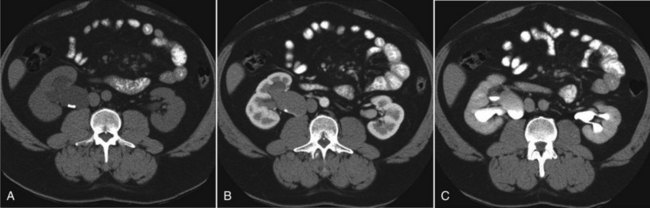

CT scan is frequently obtained for any patient presenting with acute flank pain (Fielding et al, 1997; Dalrymple et al, 1998; Vieweg et al, 1998) (Fig. 41–3). Moreover, CT scans provide detailed anatomic and functional information to aid in diagnosis of UPJ obstruction (Fig. 41–4A-C). Both ultrasonography and CT scanning also have a role in differentiating acquired causes of obstruction such as radiolucent calculi or urothelial tumors. In neonates and infants, the diagnosis of UPJ obstruction has generally been suggested either by routine performance of maternal ultrasonography or by the finding of a flank mass. In either setting, renal ultrasonography is usually the first radiographic study performed. Ideally, ultrasonography should be able to visualize dilatation of the collecting system to help differentiate UPJ obstruction from multicystic kidney and determine the level of obstruction. UPJ obstruction and multicystic kidneys are distinguishable in the majority of cases by ultrasound alone. With UPJ obstruction, the pelvis is visualized as a large, medial sonolucent area surrounded by smaller, rounded sonolucent structures representing dilated calyces. At times, dilated calyces will be seen connecting to the pelvis via dilated infundibula (Fig. 41–5).

Typically, a clear liquid diet is initiated on postoperative day 1 and advanced rapidly. Perioperative prophylactic antibiotic coverage is maintained. The Foley catheter is usually removed 24 to 36 hours postoperatively, and the surgical drain is removed before hospital discharge if the drain output remains negligible. If the drain output increases after the Foley catheter removal, the Foley catheter should be replaced for 7 days to eliminate urinary reflux along the stent in the treated ureter and decrease urinary extravasation at the ureteropelvic anastomosis. The ureteral stent is typically removed 4 to 6 weeks later in an outpatient setting, and follow-up including the use of imaging studies such as diuretic renal scan is performed as for any open pyeloplasty. Most of the complications of laparoscopic pyeloplasty are similar to those of general laparoscopic procedures including colonic injury, hemorrhage, ileus, pneumonia, congestive heart failure, thrombophlebitis, and urinoma formation. In the first 100 cases of laparoscopic pyeloplasty performed at Johns Hopkins (Jarrett et al, 2002), such complications occurred in 12% of the patients. Another large-scale review involving 189 cases of laparoscopic pyeloplasty identified approximately 2% to 2.3% intraoperative complication rate and 12.9% to 15.8% postoperative complication rate (Rassweiler et al, 2008). A typical postoperative appearance of a laparoscopic pyeloplasty patient is illustrated in Figure 41–15.